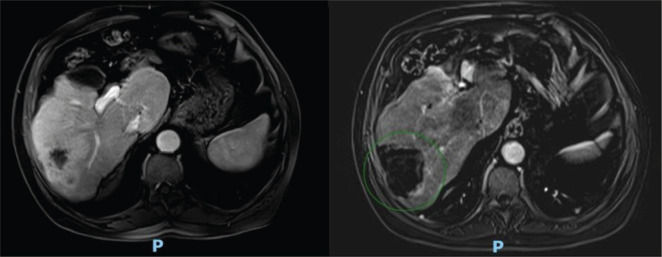

Methods: We reported a case of a 64-year-old male with locally advanced LC who developed oligometastatic disease in the bones and liver 21 months after concurrent cisplatin-based chemoradiotherapy. Initially, due to negative PD-L1 expression, the patient was treated docetaxel, cisplatin and cetuximab combination. Chemotherapy after 10 months, new hepatic progression was confirmed by biopsy. Given the asymptomatic, single-site progression in a cirrhotic liver, microwave ablation was performed. Isolated bone progressions were treated with stereotactic body radiation therapy at 2 and 4 months, and nivolumab replaced cetuximab.

Results: The patient has shown no evidence of disease progression for 22 months, with excellent tolerance.

Conclusion: The synergy between nivolumab and local therapies appears promising for managing oligometastasis in laryngeal cancer.